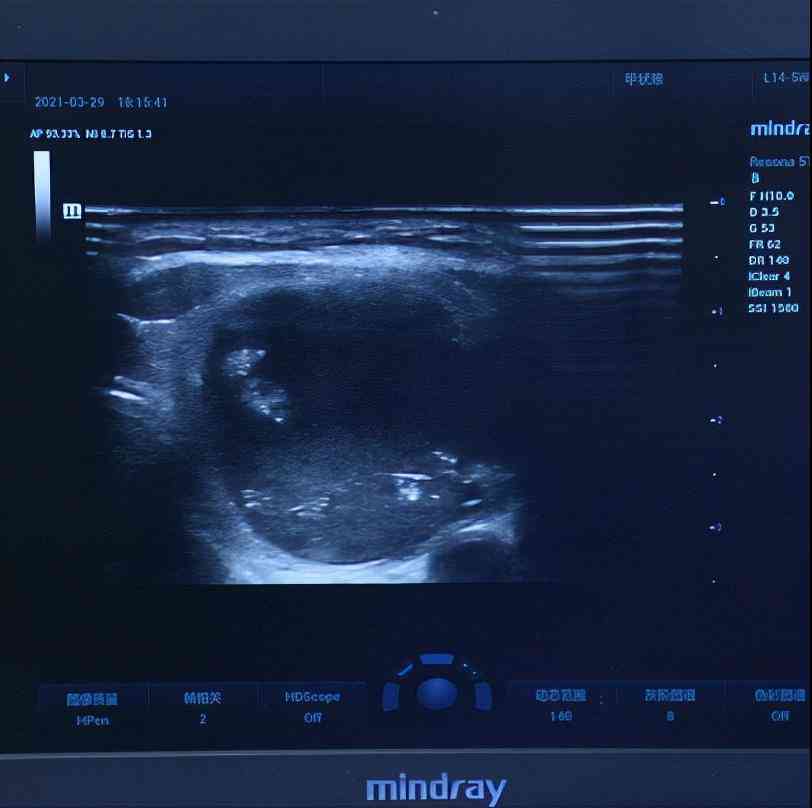

四维彩超出来,发现葛女士还有3mm的一个小结节,这个结节的评分很低,良性的可能性很大,我跟她说如果不想做手术可以先观察,等长大一点了做微创消融术也是可以的。

但一定要定期复查,因为有的结节长得很快,也有可能会恶变,所以观察并不是真的就什么都不做,放着不管的意思。